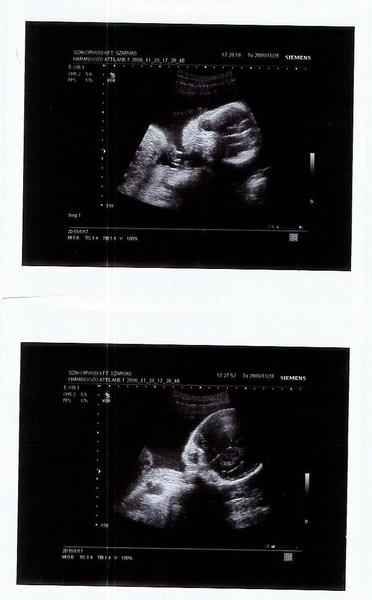

Úgylátszik végképp cserben hagyott a megérzésem, mikor mondta a doki, hogy valami van ott, el se akartam hinni. Aztán sikerült nagytotálban megnézni a kis kukacát meg a zacsit is, tehát 1000000%. Hogy is mondjam, [u]egyáltalán nem csalódtam[/u], mert nem, de meglepett. De ennek most annyira örülök. Mintha másodszorra élném át a + teszt örömét. Nagyon érdekes.

Próbálok visszaolvasni, és teszek majd fel képet is a fiatalúrról.